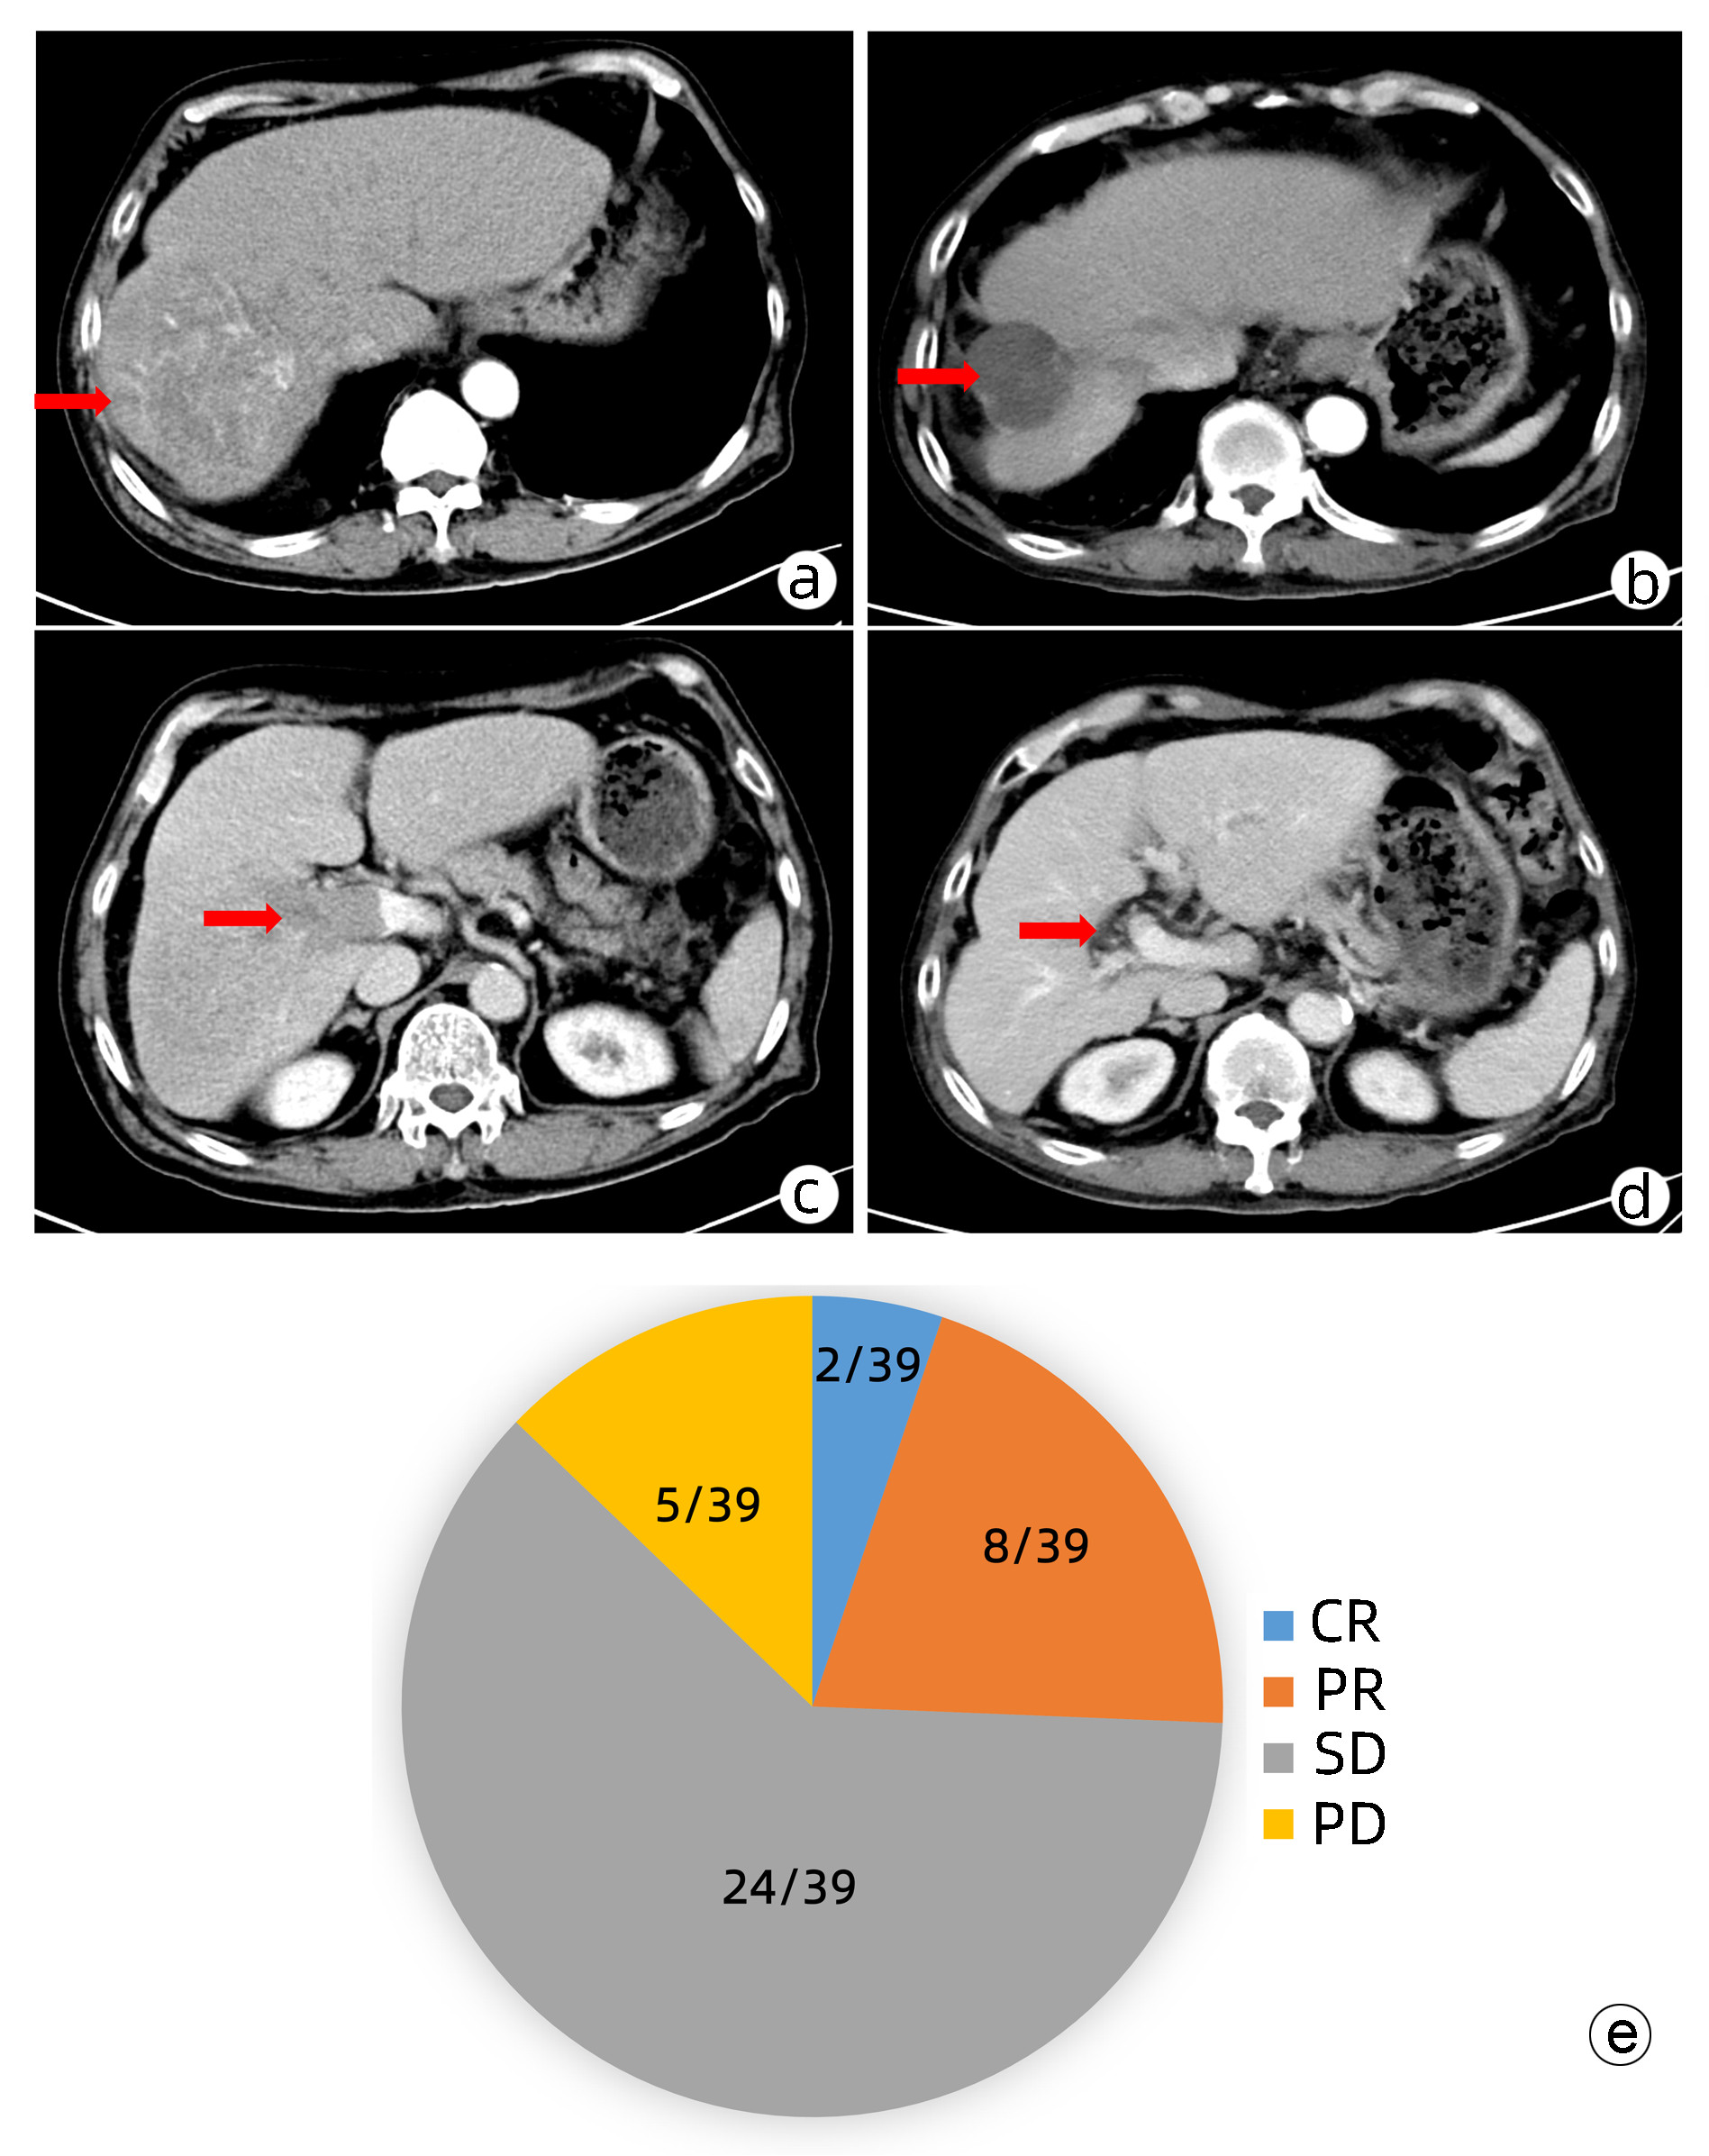

Efficacy of hepatic arterial infusion chemotherapy and its multimodality therapeutic regimens in treatment of patients with advanced hepatocellular carcinoma and related prognostic factors

Wencong DAI, Mengya ZANG, Guosheng YUAN, Qi LI, Rong LI, Wenli LI, Shuyu DONG, Jinzhang CHEN

2023, 39(7): 1592-1599. DOI: 10.3969/j.issn.1001-5256.2023.07.013

Abstract(1478) HTML (1038) PDF (2254KB)(93)

Abstract:

Objective  To investigate the efficacy of continuous hepatic arterial infusion chemotherapy (HAIC) with the FOLFOX regimen and its multimodality therapeutic regimen in the treatment of patients with advanced hepatocellular carcinoma, as well as the influencing factors for prognosis.  Methods  A retrospective analysis was performed for the clinical data of 66 patients with advanced hepatocellular carcinoma who received continuous HAIC with FOLFOX regimen in Nanfang Hospital, Southern Medical University, from September 2018 to November 2021. The patients were observed in terms of objective response rate (ORR), disease control rate (DCR), median progression-free survival (mPFS), and median overall survival (mOS) after treatment, and treatment-related adverse reactions were recorded. For the patients with portal vein tumor thrombus, the effect of the treatment on portal vein tumor thrombus was assessed. The Kaplan-Meier method was used for survival analysis, and the Cox regression analysis was used to investigate the influencing factors for prognosis.  Results  According to the RECIST1.1 criteria, FOLFOX-HAIC and its multimodality therapeutic regimen achieved an ORR of 33.3% (22/66) and a DCR of 86.4% (57/66) in the treatment of 66 patients with advanced hepatocellular carcinoma, with an mPFS time of 8.2 months and an mOS time of 22.1 months. Among the 39 patients with portal vein tumor thrombus, 2 achieved complete remission, 8 achieved partial remission, 24 achieved stable disease, and 5 had disease progression, with an ORR of 25.6% (10/39) and a DCR of 87.2% (34/39). The main adverse reactions included gastrointestinal reactions (16.7%, 11/66), pyrexia (12.1%, 8/66), liver area pain (10.6%, 7/66), bone marrow suppression (3.0%, 2/66), and contrast agent allergy (3.0%, 2/66), and there were no grade > Ⅳ toxic or side effects or deaths caused by such complications. The Cox regression analysis showed that extrahepatic metastasis (hazard ratio [HR]=2.668, 95% confidence interval [CI]: 1.357-5.245, P < 0.05) and prothrombin time (PT) (HR=1.282, 95%CI: 1.080-1.630, P < 0.05) were independent risk factors for PFS, and aspartate aminotransferase level (HR=1.008, 95%CI: 1.002-1.013, P < 0.05) and PT (HR=1.303, 95%CI: 1.046-1.630, P < 0.05) were independent risk factors for OS.  Conclusion  FOLFOX-HAIC and its multimodality therapeutic regimen has a certain clinical effect with controllable adverse reactions in the treatment of advanced hepatocellular carcinoma.